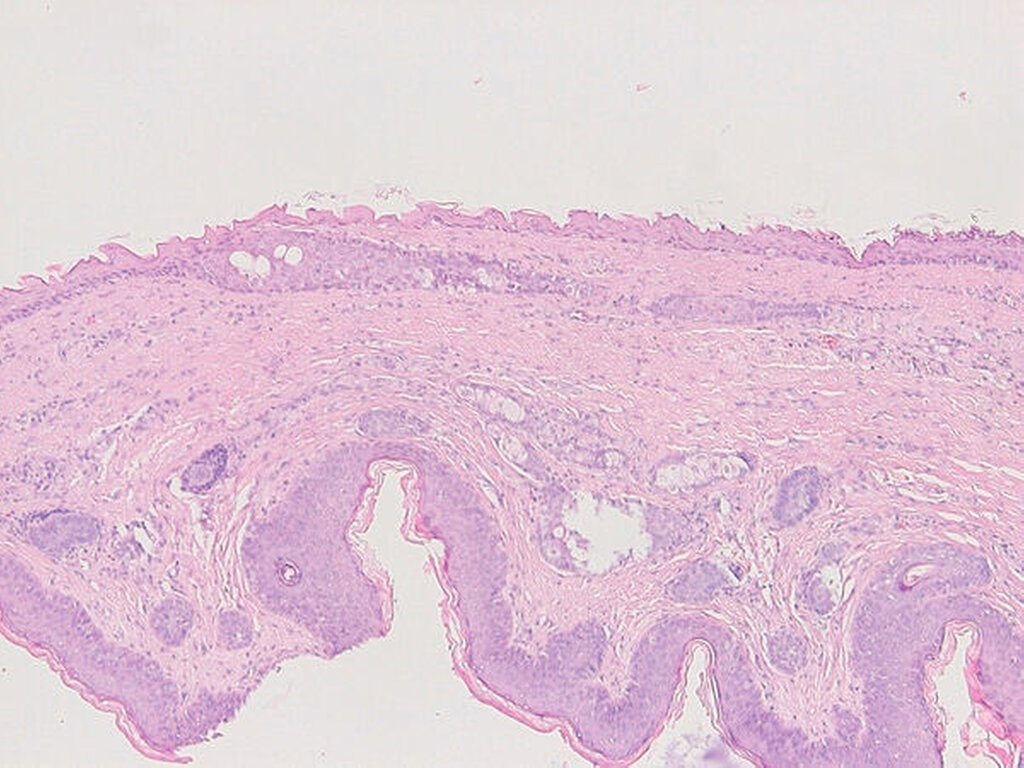

Zwei Wochen nach der Erstvorstellung erfolgte die komplikationslose Resektion in Intubationsnarkose (Abbildung 4). Im histologischen Bild sieht man eine vollständig entfernte Dermoidzyste (Abbildung 5). Bei der Nahtentfernung in Sedierung eine Woche nach der operativen Intervention wurde zeitgleich zum sicheren Ausschluss einer Meningomucozele und weiterer Pathologien eine Magnetresonanztomografie durchgeführt. Hierbei waren keine Residuen der Dermoidzyste sowie keine Fistelung nach intrakraniell auffällig. In den klinischen Nachkontrollen zeigten sich regelhafte und reizlose Wundverhältnisse (Abbildung 6).

Entwicklungsgeschichtlich entstehen Dermoidzysten aus Gewebe, das während der Embryonalentwickung versprengt wird. Deshalb können Dermoidzysten vielerlei Gewebsanteile aller Keimblätter enthalten, wie beispielsweise Hautanhangsgebilde, Zähne, Haare und Knochen. Sie besitzen zudem eine derbe Kapsel, die mit teigiger Masse gefüllt ist. Eine genetische Prädisposition und ein Zusammenhang mit kraniofazialen Fehlbildungen werden derzeit diskutiert [Van Wyhe et al., 2016; Rodrigues et al., 2017; Cajozzo et al., 2019].